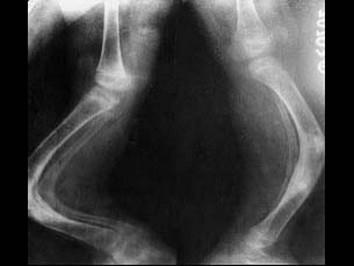

问题 女,2岁,有蓝色巩膜、听力障碍,四肢畸形等,请结合所提供图像,选择最佳选项 ( )

选项 A、呆小病 B、成骨不全 C、维生素C缺乏病 D、软骨发育不全 E、维生素D缺乏病

答案 B